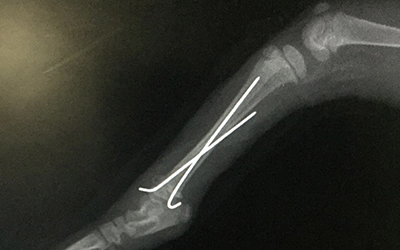

Endlich mit Bohrmaschine!

Fachinfo bohrerDa sich die Anfragen für Osteosynthesen häufen, habe ich endlich eine Bohrmaschine angeschafft. Wir bieten damit Bohrdrahtosteosynthesen z.B. zur Versorgung von Epiphysenfrakturen oder Zehenserienfrakturen an und können Fixateurs externes anbringen. Besonders bei Jungtieren sowie kleinen Heimtieren sind so erfolgreiche orthopädische Operationen möglich.